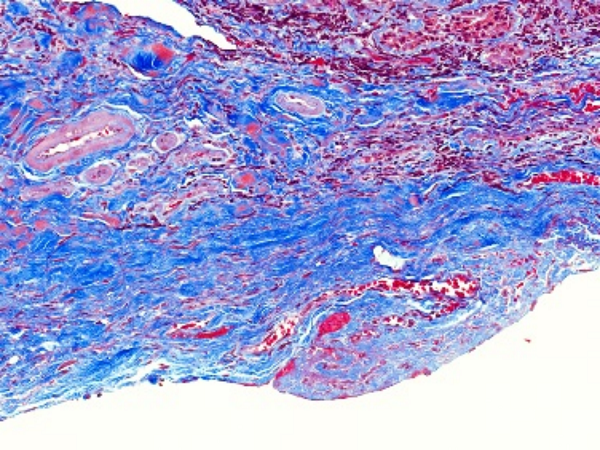

Masson染色是一种用于显示组织中纤维成分的特殊染色方法,主要用于区分胶原纤维和肌纤维,在病理学和组织学研究中有广泛的应用。**一、染色原理**1. 试剂作用 - **酸性复红**:它是一种酸性染料,能够将细胞质、肌纤维等染成红色。在染色过程中,酸性复红与肌纤维中的碱性蛋白结合,使肌纤维呈现出红

18326618418 立即咨询Masson染色是一种用于显示组织中纤维成分的特殊染色方法,主要用于区分胶原纤维和肌纤维,在病理学和组织学研究中有广泛的应用。

**四、结果观察与分析**

1. 细胞核

- 经过Weigert铁苏木精染液染色后,细胞核呈现黑色。可以观察细胞核的大小、形状、位置以及核内结构(如核仁),这有助于判断细胞的类型和状态。

2. 肌纤维

- 被酸性复红染色后呈红色,通过观察肌纤维的分布、走向和形态,可以了解肌肉组织的结构和功能。例如,在心肌组织中,心肌纤维呈分支状,相互连接成网状;在平滑肌组织中,肌纤维呈长梭形,排列较为规则。

3. 胶原纤维

- 被苯胺蓝染色后呈蓝色。可以观察胶原纤维在组织中的分布和含量,这对于研究组织的纤维化程度、创伤修复等过程具有重要意义。例如,在肝脏纤维化的组织中,会出现大量蓝色的胶原纤维增生。